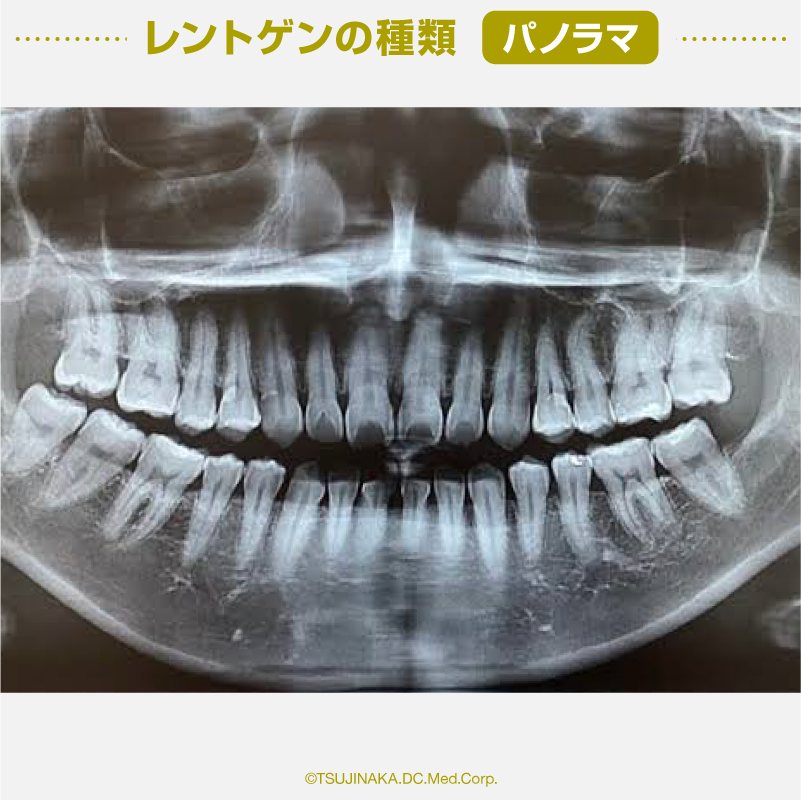

パノラマ

全ての歯を中心に、顎の全体を一度に撮影するものです。一枚の写真で歯の状態や、上下の顎の骨や顎の関節など、全体を大まかに把握することができます。